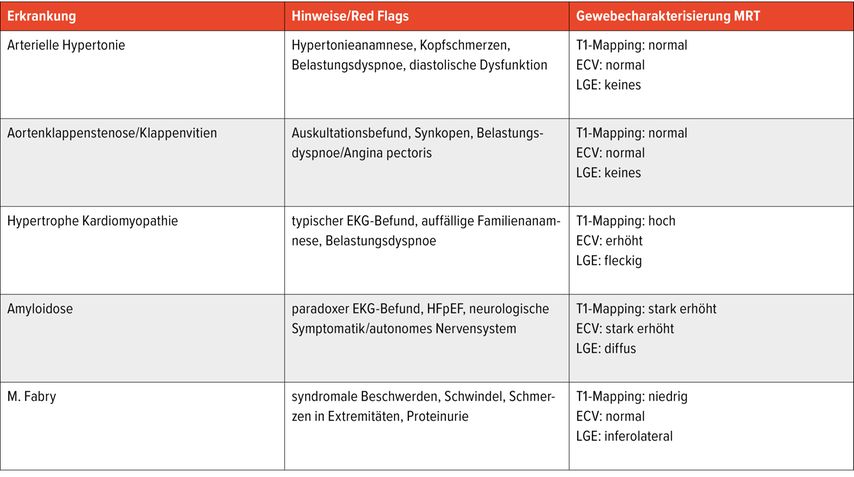

Typische Symptome können je nach Erkrankung auftreten (Tab.1). Bei HCM bzw.HOCM sind vor allem Patient:innen mit Obstruktion (ab ca. 30mmHg) von Symptomen betroffen, etwa von Dyspnoe, Schwindel, Synkopen oder Palpitationen. Typischerweise ist auch die Familienanamnese auffällig, da oft mehrere Familienmitglieder betroffen sind. Aufgrund des erhöhten Arrhythmierisikos ist die HCM bzw. HOCM einer der häufigsten Gründe des plötzlichen Herztods bei jungen Menschen.6

Über die Bestimmung des extrazellulären Volumens (ECV) kann außerdem der Verdacht auf eine Speichererkrankung erhärtet werden (Abb.4). Auch seltene Erkrankungen wie M.Fabry haben charakteristische Befundkonstellationen im kardialen MRT (Tab.1).12

Tab. 1: Ursachen für LVH, häufige Symptome und typische MRT-Befundkonstellationen (modifiziert nach Martinez-Naharro et al. 2020)12